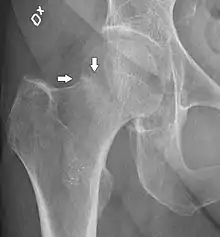

В большинстве случаев достаточно выполнения рентгенограммы в прямой проекции. В ситуациях, когда есть подозрение на перелом шейки бедра, но оно не выявлено на рентгеновском снимке, следующим методом исследования является КТ. В редких случаях для подтверждения диагноза используется МРТ - диагностика.

Случай, демонстрирующий возможный порядок исследования изначально незаметных проявлений: